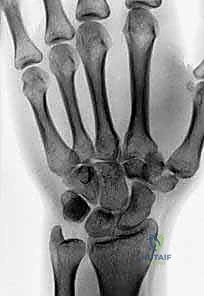

يتكون الرسغ من ثماني عظام صغيرة تُعرف بعظام الرسغ (Carpal bones)، مرتبة في صفين (صف قريب وصف بعيد). بينما يستحوذ العظم الزورقي (Scaphoid) على النصيب الأكبر من الكسور والاهتمام الطبي، فإن العظام السبعة الأخرى تلعب أدواراً حاسمة لا تقل أهمية.

التشخيص هو المرحلة الأهم. الأشعة السينية العادية (X-rays) قد لا تظهر هذه الكسور الدقيقة في البداية بسبب تراكب عظام الرسغ. هنا تبرز خبرة الأستاذ الدكتور محمد هطيف في صنعاء، حيث يعتمد على بروتوكولات تشخيصية عالمية.

- الأشعة السينية بوضعيات خاصة: أخذ صور بأكثر من زاوية لفك تراكب العظام.

- الأشعة المقطعية (CT Scan): المعيار الذهبي لتشخيص كسور عظام الرسغ المخفية وتحديد حجم التفتت والتزحزح.